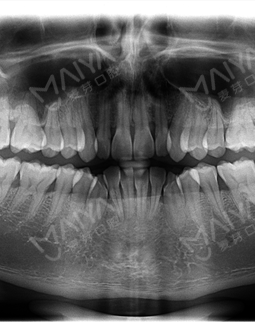

2016-11-1 口腔检查

选择麦芽口腔矫正牙齿,更多是因为口碑,当然矫牙不可能那么随便,我还是几经对比过,但麦芽口腔整体的服务以及正畸科室的规模、医生的专业性,都让我很满意。矫牙是个时间活,如果连医院都不稳定,这漫长的时间,要是有问题,我找谁呢?麦芽口腔是原来市二院口腔科主任郑苍尚教授带领组建的,看我这细致的做功课能力,初次来到麦芽口腔,真切感受到了麦芽的服务,首先导医带我挂号登记,然后张超主任为我详细检查了牙齿状况,并了解了我的个人矫牙需求。